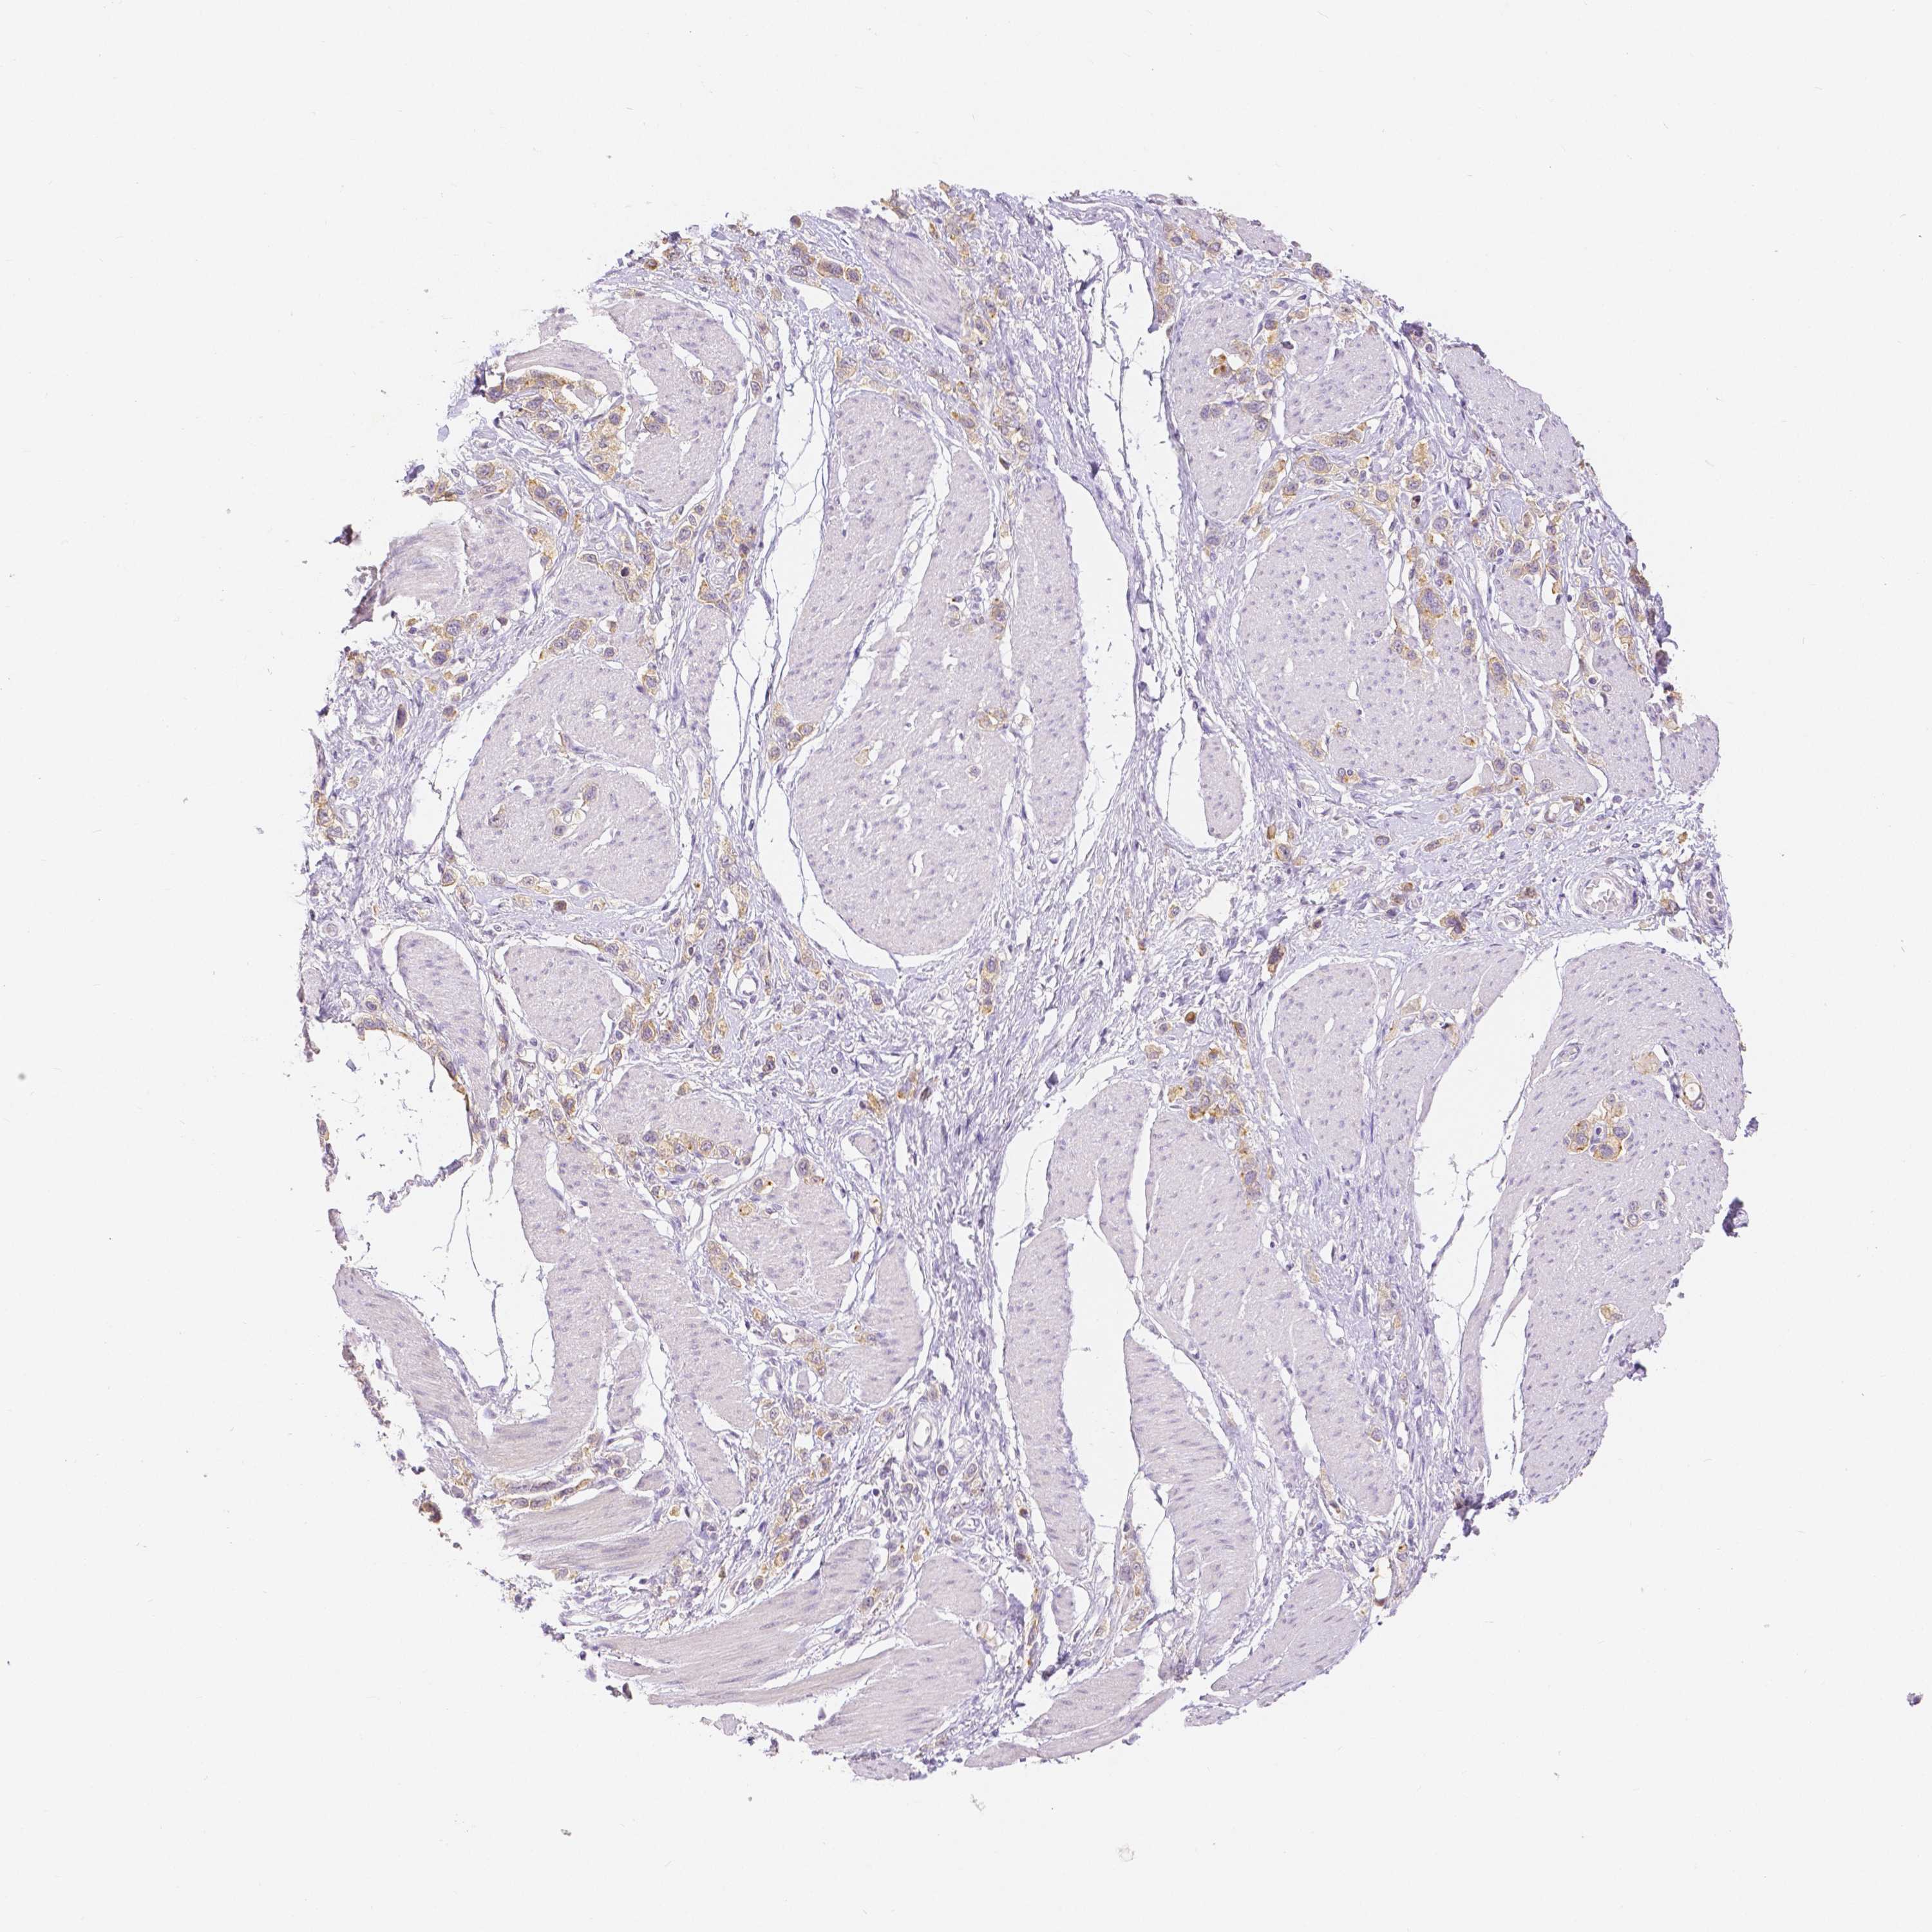

STOMACH CANCER - Protein expressioni

A mouse-over function shows sample information and annotation data. Click on an image to view it in a full screen mode. Samples can be filtered based on level of antibody staining by selecting one or several of the following categories: high, medium, low and not detected. The assay and annotation is described here.

Antibody stainingi

Antibody staining in the annotated cell types in the current human tissue is reported as not detected, low, medium, or high, based on conventional immunohistochemistry profiling in selected tissues. This score is based on the combination of the staining intensity and fraction of stained cells.

Each image is clickable and will lead to virtual microscopy that enables deeper exploration of all samples and also displays staining intensity scores, fraction scores and subcellular localization as well as patient and tissue information for each sample.

HPA005933

CAB013075

CAB068212

CAB068213

CAB068214

Staining

High

Medium

Low

Not detected

Intensity

Strong

Moderate

Weak

Negative

Quantity

>75%

75%-25%

<25%

None

Location

Nuclear

Cytoplasmic/membranous

Cytoplasmic/membranous,nuclear

Adenocarcinoma, NOS

Adenocarcinoma, High grade